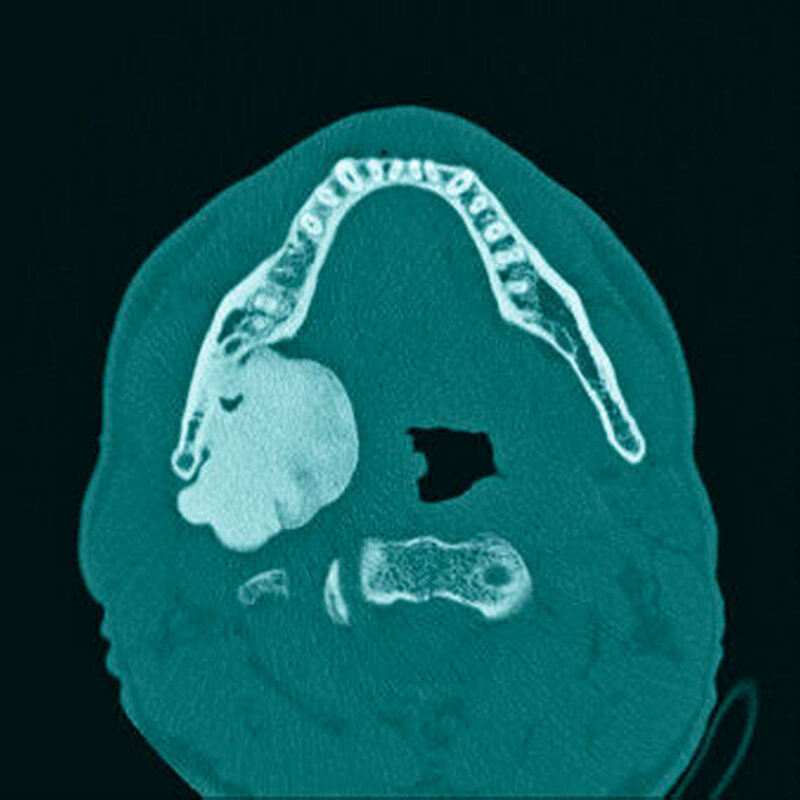

Im mitgebrachten alio loco erstellten Orthopantomogramm war eine gut abgrenzbare, ovale, homogene Verschattung zu sehen, welche sich im Bereich des rechten Kieferwinkels, in dorsaler und kranialer Richtung über diesen hinaus sowie im Bereich des aufsteigenden Unterkieferastes bis kaudal unter die Incisura semilunaris erstreckte (Abbildung 1). Computertomografisch war ausgehend von der medialseitigen Corticalis des Angulus mandibulae rechts eine irregulär, angedeutet rundlich konfigurierte, glatt begrenzte knöcherne Raumforderung von circa 4,4 x 3,3 x 4,7 cm Größe zu sehen (Abbildungen 2 und 3). Diese führte zu einer Verlagerung der Anatomie, insbesondere zu einer Vorwölbung der rechtsseitigen Oropharynxseitenwand (Abbildung 4). Es bestanden keine Hinweise auf eine knöcherne Destruktion oder auf eine Lagebeziehung zu einem Zahn.